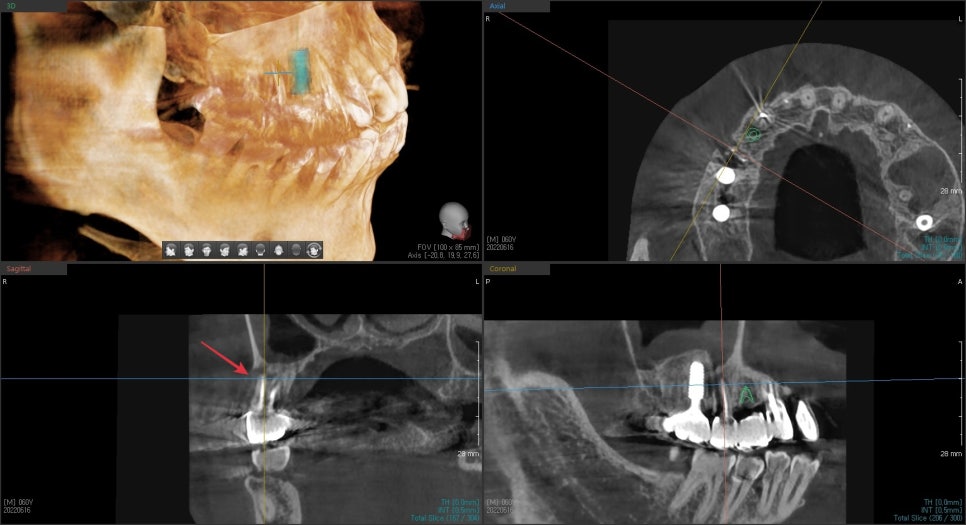

다행히 수술 약 4개월 후 3D CT에서

임플란트 주변으로 흰색으로 보이는 뼈가 생성된 것을 확인할 수 있었습니다.

현재 1년이 지난 전체 사진에서도 특별한 문제는 없어 보입니다.

임플란트 수술 후 다른 환자분보다 조금 더 기다렸지만

잘 따라와 주셔서 좋은 결과가 있었습니다.